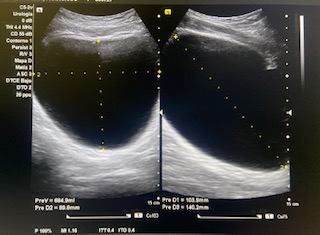

Vejiga bien repleccionada sin alteraciones a simple vista.

Volumen residual: 243 ml. Próstata de contornos regulares y ecogenicidad homogénea a simple vista. Volumen prostático: 49 cc.

En ecografía determinamos el tamaño de la próstata mayor de 20 cc, por tanto se trata de una HBP grado II. La medición del RPM nos permitió detectar que el paciente presentaba residuos elevados (243 ml).

Nueva ecografía de control en seis meses se recomienda segunda determinación dada la variabilidad de la prueba en el estudio de RPM y control clínico de STIU a pesar del tratamiento.